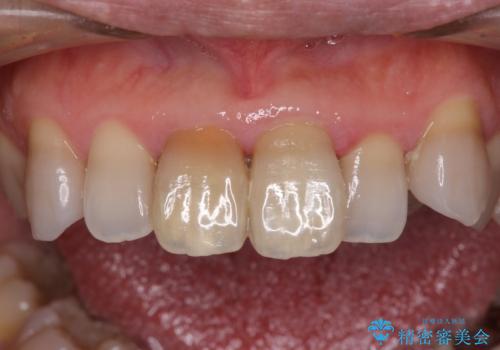

変色した前歯 オールセラミッククラウンにより審美歯科治療

- 変色した前歯2本を気にして来院された患者様です。

右側の前歯は根管治療を行い、その後2本とも歯質に近い素材の土台を植立してオールセラミッククラウンにて補綴することとしました。